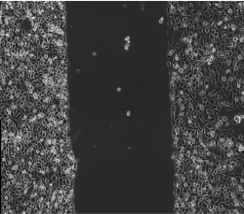

原代細胞:原代培養是直接從生物體獲取組織或器官的一(yī)部分進行培養。原代培養細胞與體內原組(zǔ)織在形態結構和功(gōng)能活動上相似性大。由於培養的細胞剛剛從活體組織分離出來,故更接近於生物體內的生活狀態。這一方法可為(wéi)研究生物體細胞的生長(zhǎng)、代謝、繁殖提供有力的手段。

腫瘤細胞:腫瘤細胞在(zài)組織培養中占有核心的(de)位置,首先癌細胞是比較容易(yì)培養的細胞。當前建立的細(xì)胞係中癌細胞係是最(zuì)多(duō)的。腫瘤細胞培(péi)養是研究癌變機理、抗癌藥檢測、癌(ái)分(fèn)子生(shēng)物學極(jí)其(qí)重要的手段(duàn)。腫瘤細胞培養對闡明和解決癌(ái)症將起著不可估量的作用。